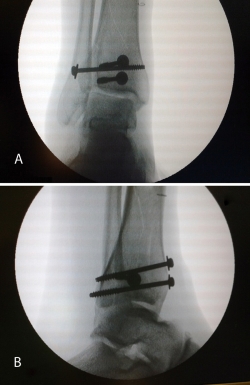

Realizamos los portales artroscópicos habituales en función de la situación de los extremos óseos de la fractura y practicamos un procedimiento idéntico al anterior: lavado, desbridamiento e identificación del foco de fractura (Figuras 12 a 16).

Figura 12. Caso 2: fractura espiroidea con afectación articular. Posicionamiento en férula de Braun. Tracción con vendas. Realización de portales.

Figura 13. Posteriormente, realizamos la limpieza del foco con cucharilla y la reducción del mismo mediante pinzas de cóndilo bajo control radioscópico/artroscópico, y fijación provisional con agujas de Kirschner.

Figura 14. A continuación, se realiza la medición y colocación secuencial de los tornillos.

Figura 15. Por último, se procede a la colocación definitiva de los tornillos.

Figura 16. Resultado final a los 4 meses.